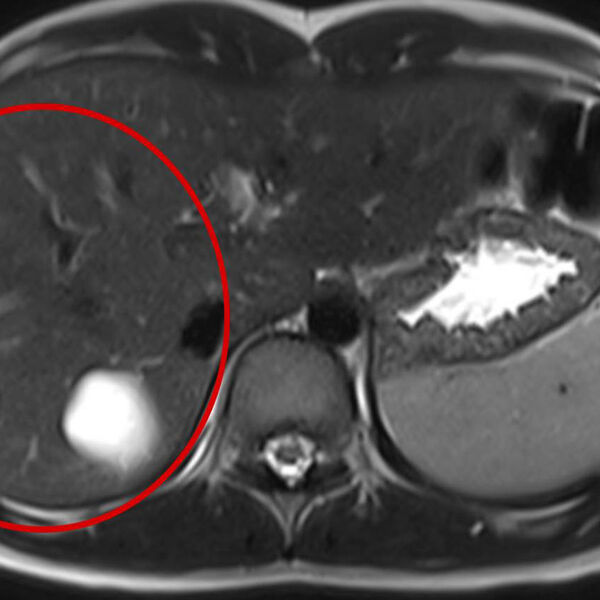

Врачи больницы имени Сперанского спасли 14-летнюю девочку с множеством паразитарных кист в печени. Об этом сообщили в пресс-службе столичного департамента здравоохранения.

Кисты медики обнаружили случайно во время планового обследования. После этого ребенка направили на операцию.

Во время вмешательства специалисты удалили пять кист с использованием лапароскопии. Через пять дней после операции пациентку выписали домой.